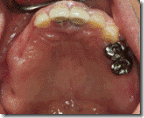

患者A先生

上顎 正面 下顎

患者B小姐

以上兩位患者口內狀況非常複雜,要制定一個好的治療計畫,

不只要考慮到患者的牙齒條件,

還要顧及患者意願、時間、金錢、評估可獲得的結果等等。

所以像這類型的Case 醫師通常在初步的溝通後會先做出一兩個不同的治療計畫,

再和患者解釋,了解患者接受程度。